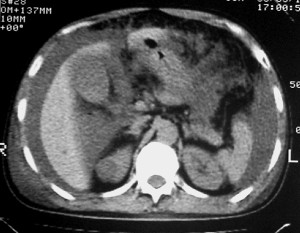

右侧肺癌术后:肝内可见多个大小不等的低密度结节影。腹腔及双侧胸腔大量积液。考虑:肺癌并胸膜及肝脏转移。

腹水,肝及右肾多发低密度影。考虑转移。

右肾及肝内多发转移瘤,胸水。

1、右肺癌术后改变。2、双侧胸水、腹水。3、多发性肝囊肿,右侧肾囊肿。

目前转移或复发的依据不足,术后才一个月,个人认为还是让临床去判断,而且需结合术前常规检查,有无肝肾囊肿;另外有一个疑问:肝胃间隙内团状软组织影是胃食管交接区吗,胃腔太小了吧,有无手术史请楼主告知.